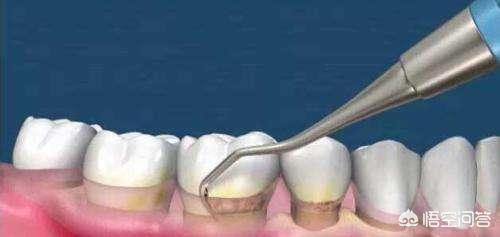

原因:1) 細菌の蓄積。細菌の代謝産物が歯の表面に付着し、通常のブラッシングでは除去できない。 2) .歯石 歯石とは歯の表面に沈着したミネラル化したプラークを指し、その沈着部位や性質によって歯肉縁上歯石と歯肉縁下歯石の2種類に分けられる。 (1)歯肉縁上歯石は歯肉縁上の歯面にあり、肉眼で直接確認できる。 (2)歯肉縁下歯石は、歯肉縁下の歯根面、歯肉ポケットや歯周ポケットに存在し、肉眼では直接見ることができず、歯周炎になりやすい3)。外傷性咬合 咬合時に、咬合力が大きすぎたり、異常な方向にかかったりして、歯周組織が耐えられる合力を超え、歯周組織に損傷を与える咬合を外傷性咬合という。外傷性咬合には、咬合時の早期接触、歯列との干渉、夜間の歯ぎしりなどがある。 4).また、食物の挟み込みも歯周組織の炎症の一因となる。歯周炎になると、しばしば1本以上の歯が抜けてしまう。

治療:ゆるみが2mm以下であれば、歯肉縁上清掃や歯肉縁下掻把、咬合調整、食物挟み込みの除去、抗生物質の使用、膿瘍の切開排膿などを行うが、ゆるみが2mm以上であれば抜歯をお勧めする。

定期的なフルマウスクリーニング、必要に応じて歯肉縁下のスクレイピングとルートプレーニング、重度の歯周炎には歯周フラップ手術を行います。積極的な治療によってのみ、歯周病の進行を効果的に遅らせることができるのです。

歯周炎で歯が抜けた場合、歯石がたくさん付着していたり、歯肉の退縮で黒い三角形が現れたり、歯肉から出血したりすることで現れます。歯周病治療を行うには、最も基本的な方法は、超音波洗浄、歯肉縁下スクレイピングで歯の周りの歯石や歯垢など炎症の原因となるものを取り除くことです。また、歯のセルフクリーニングを入念に行う(歯磨きのたびに必ずフロスを使用する)ほか、定期的な検診を受け、病変の後退が遅れている場合は、状況に応じて歯周外科治療を受けることになりますが、この治療の主な目的は、歯の周囲の炎症を完全に除去し、治癒を促進することです。